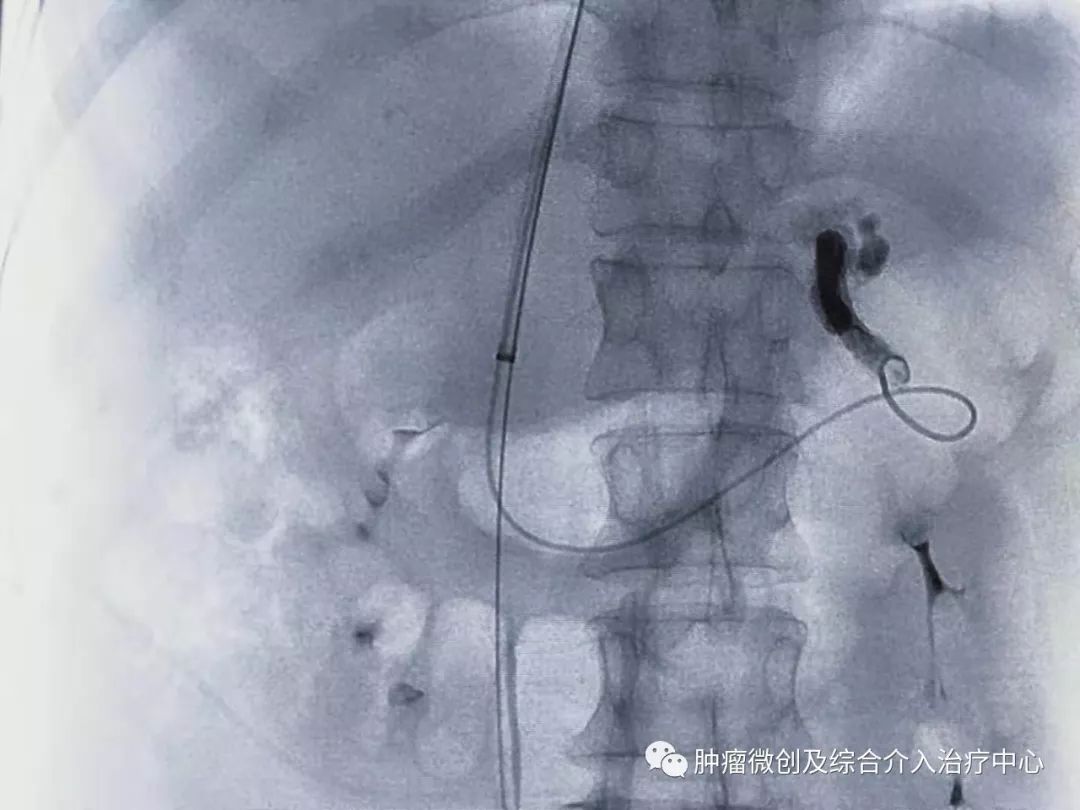

栓塞消化道出血责任血管:

再次造影可见:门脉血流流向-体静脉达到分流目的,术前侧压力42,术后25,门脉压力明显降低,达到防止再次出血目的。